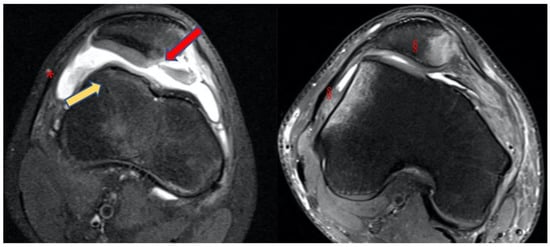

- Bone bruises on the medial side of the patella and the lateral condyle, which indicate with certainty the occurrence of a recent patellar dislocation;

- Osteochondral fracture with possible loose bodies, which are important to rule out, especially in skeletally immature patients. If the osteochondral fracture has a sufficient size (5–10 mm on MRI), urgent reduction and fixation, either open or arthroscopically, must be considered [25];

- Trochlear dysplasia, for which axial images are needed to achieve a correct classification according to the Dejour classification [9];